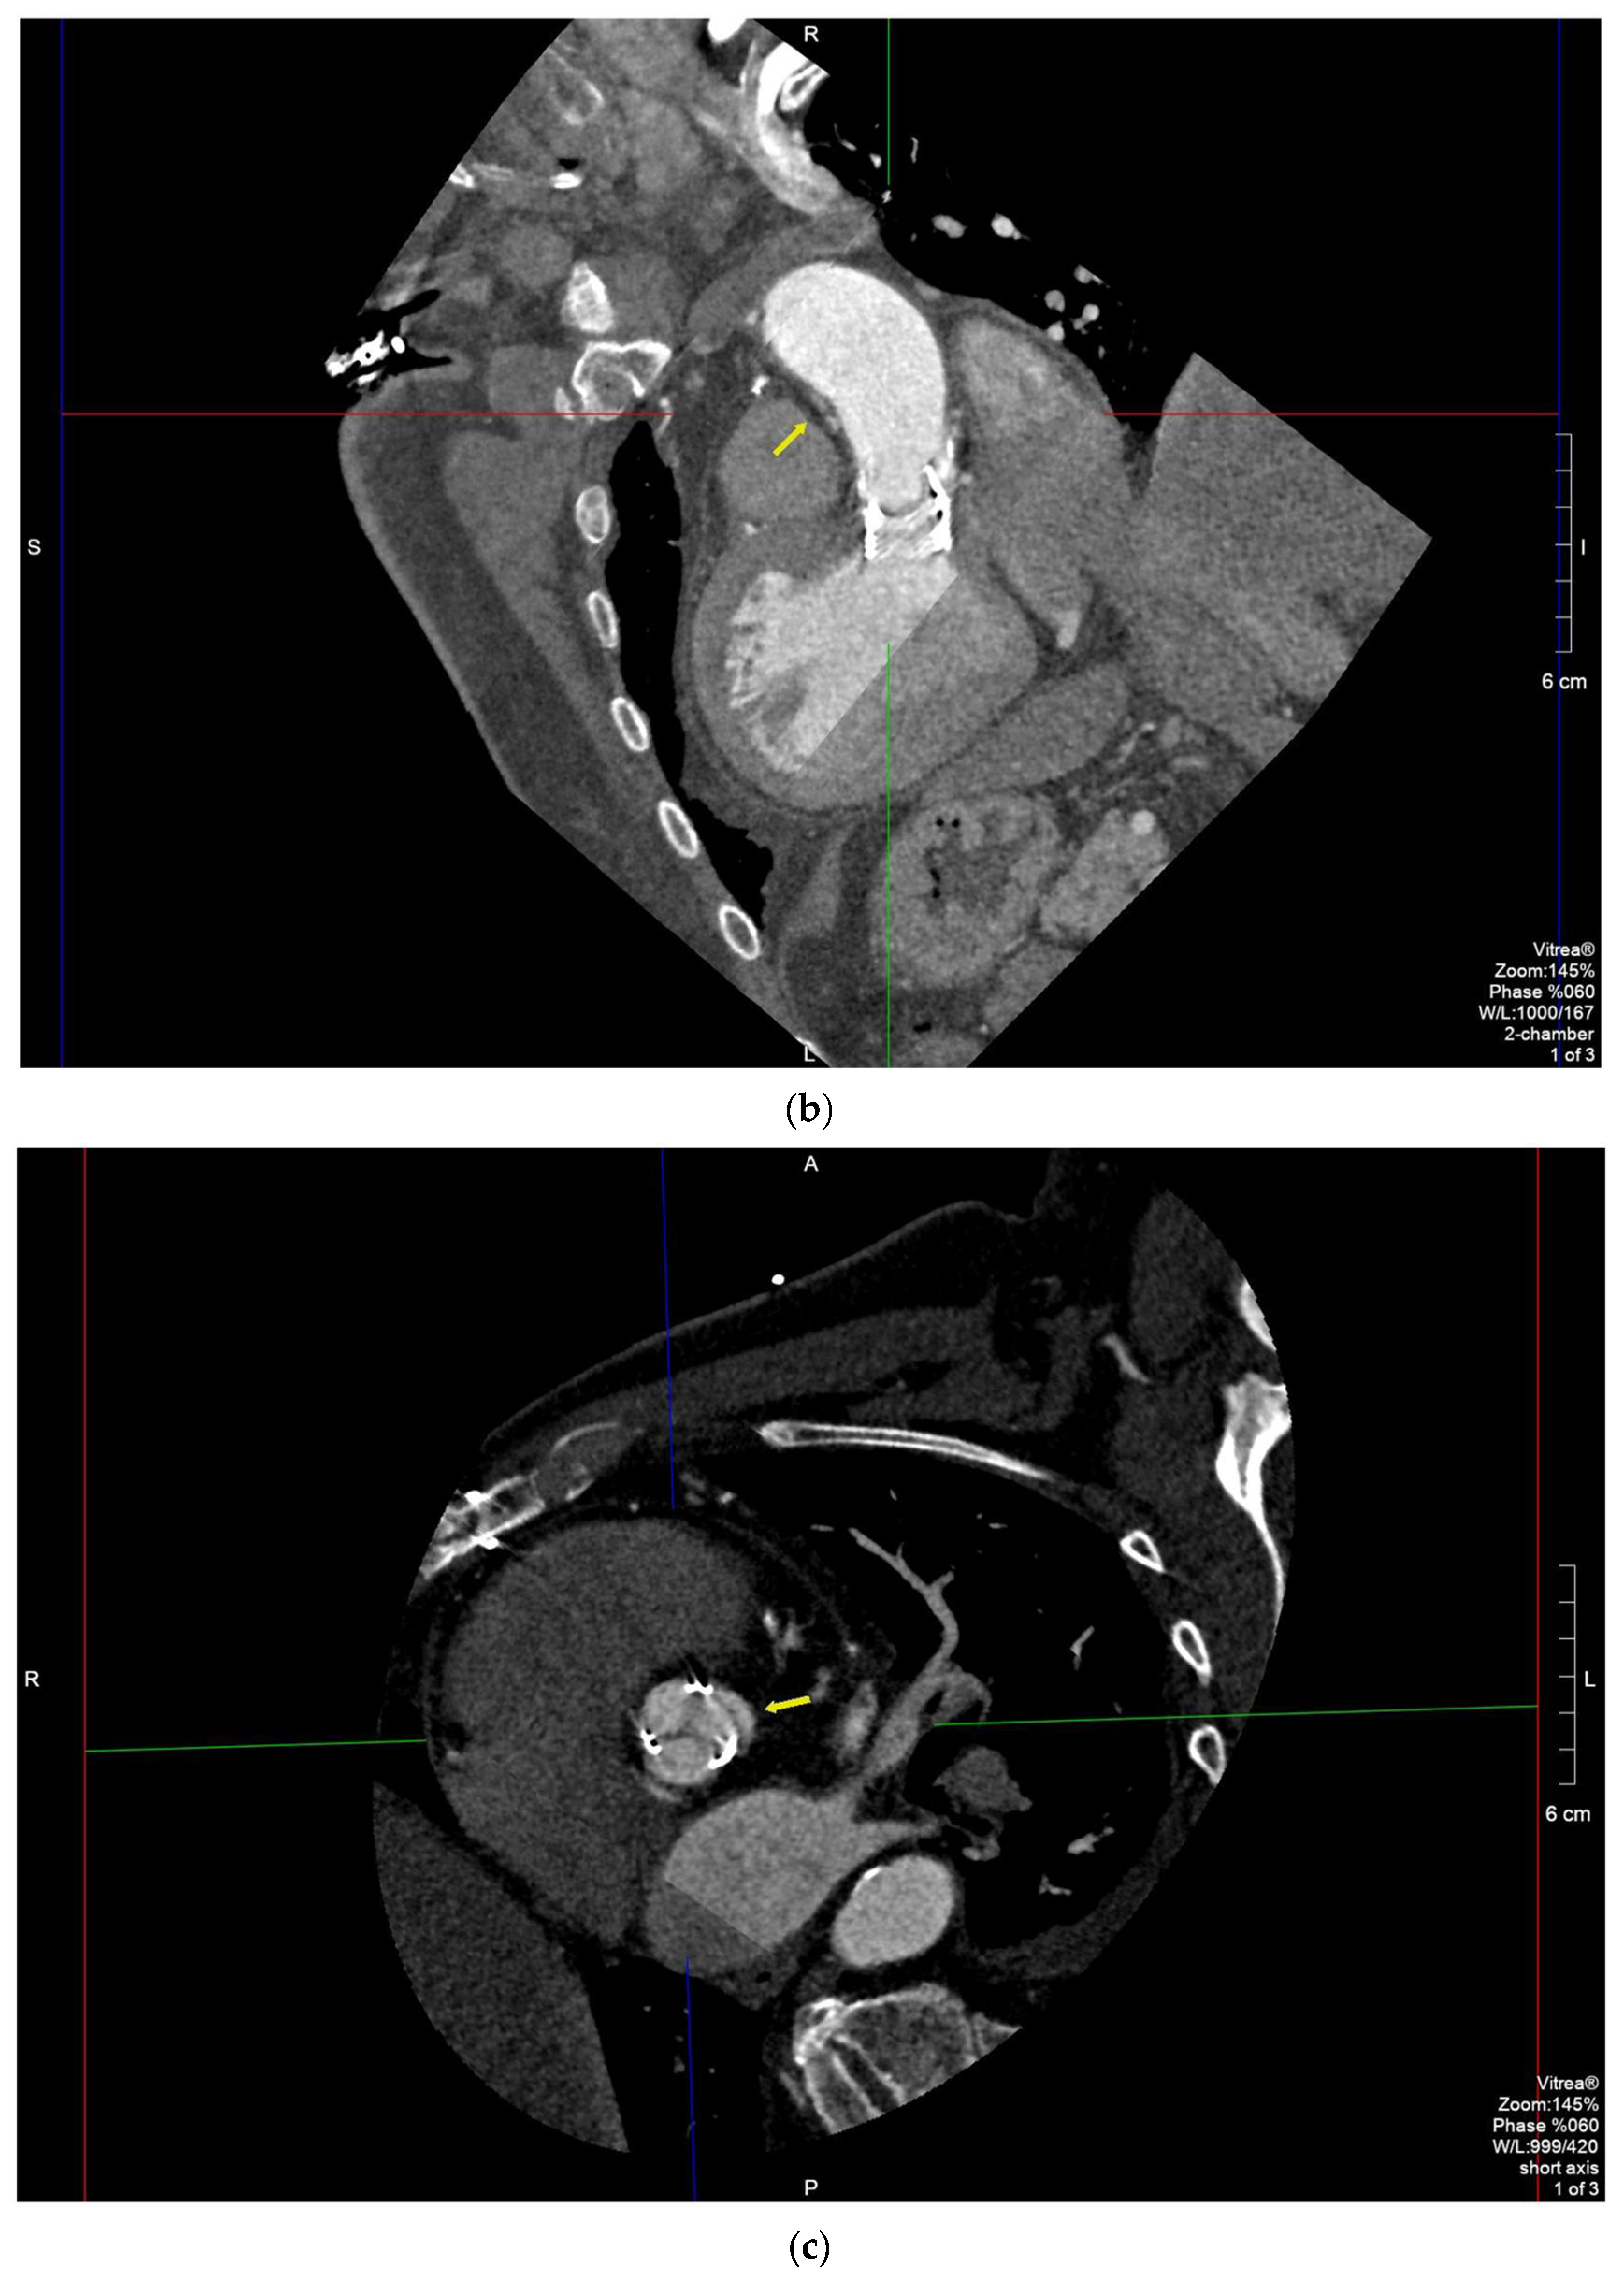

2.1. Case 1

2.2. Case 2

2.3. Case 3